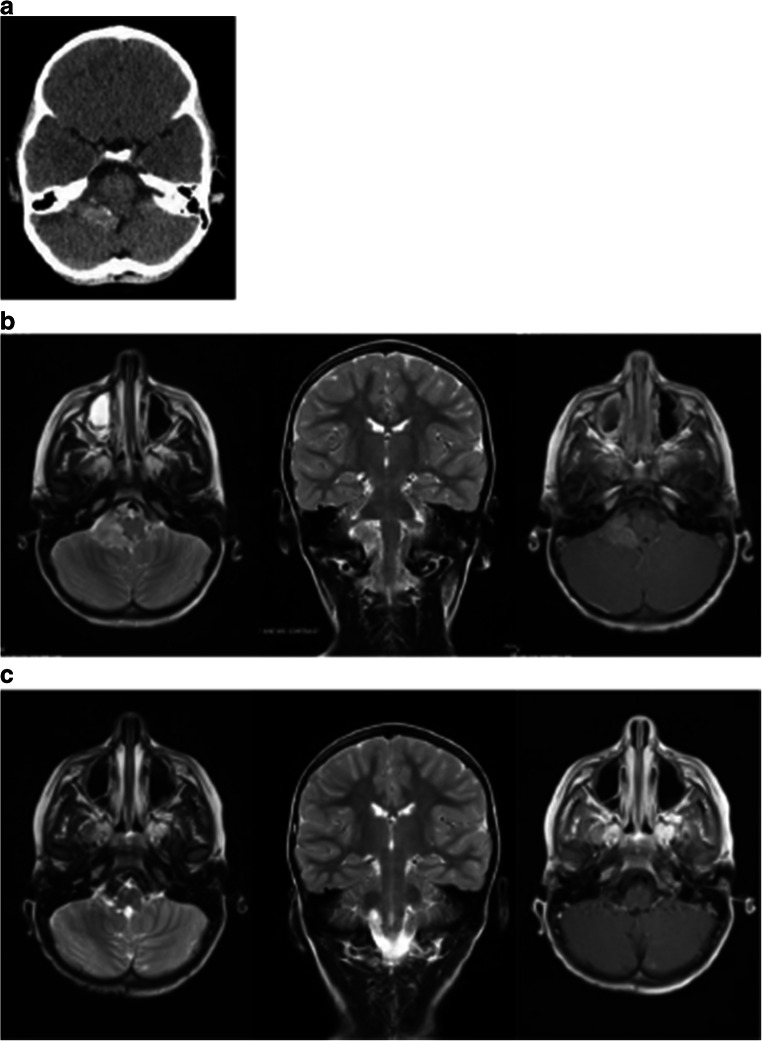

Case 8

A 5-year-old male had a minor head-on collision followed by headaches. CT without contrast obtained at that time showed a lobulated hyperdense mass at the right CPA (Fig. 3a). Subsequent MRI showed a lobulated mass, hyperintense on T2, and homogeneously enhancing right CPA lesion (Fig. 3b). There were no signs of hydrocephalus. His neurological examination was intact.

Fig. 3.

Case 8. a Non-contrast CT showing a hyperdense right cerebellopontine angle lesion centered around the foramen of Luschka. b Preoperative T2-weighted MR; axial (left) and coronal (center) images and contrast enhanced T1-weighted axial image (right) show homogeneous enhancement of a CPA choroid plexus papilloma. c Postoperative T2-weighted MR; axial (left) and coronal (center) images and T1 with contrast (right) show a resolution of a CPA choroid plexus papilloma

He underwent a posterior fossa craniotomy tumor resection. It was done through a hockey stick incision as outlined previously [11]. A homogeneous solid tumor was present in the right cerebellomedullary fissure of the CPA. The nerve roots of 7–10th cranial nerves of the right side were displaced ventrally. Medially the right-sided PICA gave rise multiple feeders to the tumor. The tumor appeared to be present in the expanded lateral recess with the tela choroidea surrounding it dorsally. There was no brainstem involvement. A piecemeal resection was done under surgical microscope, and a gross total resection was achieved. Pathology was consistent with CPP.

The patient showed no postoperative neurological deficits. Presently, 21 months after the tumor resection, he shows no signs of tumor recurrence (Fig. 3c).